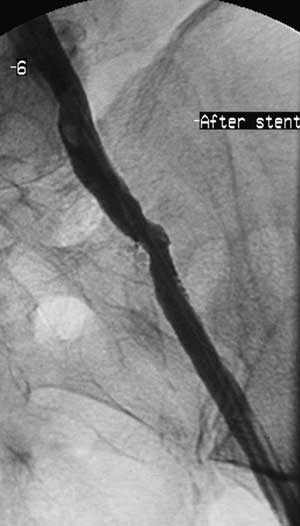

Имплантация артериального стента Белорусского производства.

Рис. 6. Контрольная артериограмма после стентирования.